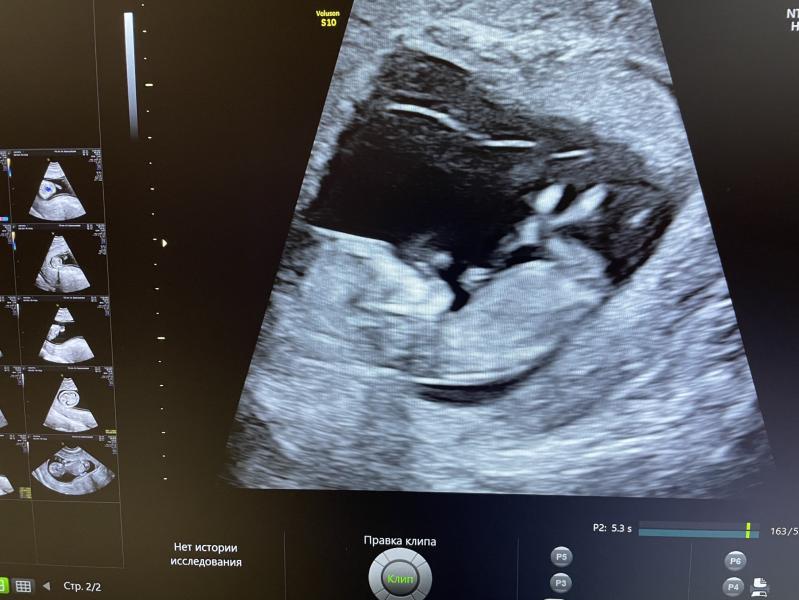

Всем привет! Ходила на первый скрининг, и это было ужасно. Думала будет классно, увижу ребенка, узнаю что и как. В итоге - очень грубое отношение, больно давили, жестко надавливали, короче ужасные ощущения. Медсестра хамка ужасная, доктор слова не проронила. В конце сухо «результат у врача через 10 дней»

Это нормальная практика? Я ожидала совсем иного, что хотя бы мужа пустят на малыша посмотреть. Совсем не думала, что будет так ужасно и неприятно.

Вот сняла экран, тк врач отказалась распечата...